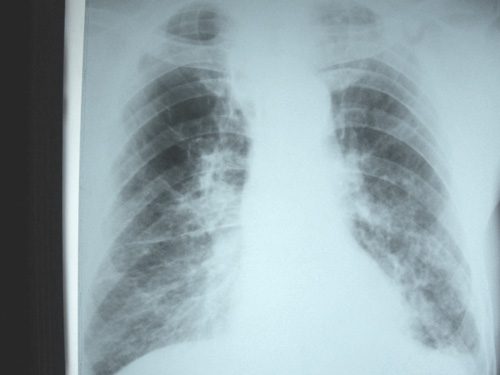

老年男性,70岁。煤矿工人20年。一周前咳嗽、发烧,拍x片考虑矽肺可能。始终咳嗽行ct检查,发现弥漫性病变,似感染但密度很高,细支气管肺泡癌无法排除,请老师给予指点。

一般矽肺多为双肺融合状,团块状高密度结节影.并散在多处小结节影.可这个病人只表现在单肺,并没有融合结节影.一周前的x片没显示大片高密度影,可定位扫描时(图象忽略传了),右肺已经清晰显示大片高密度影.作比较感觉是新病灶.可实际表现又不象,所以才拿来让各位老师看看.

ct片与平片只相隔1周时间变化太大,结合临床应该首先考虑尘肺合并感染,肺泡癌变化不会这么快,